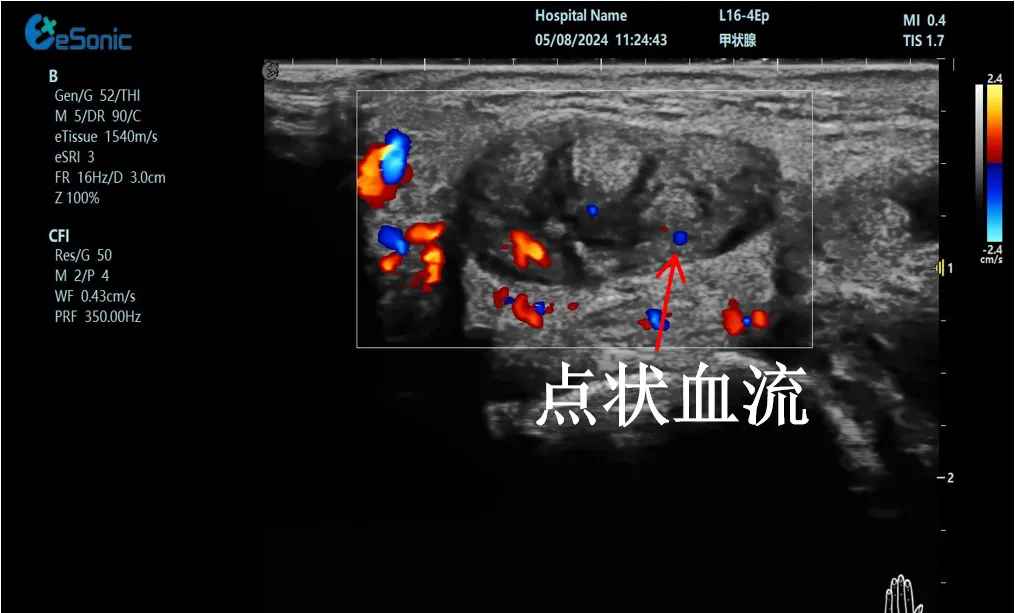

mFlow?技术在腱鞘炎诊疗中的应用

【背景】:左手腕关节第四腔室腱鞘炎。

【痛点】:普通彩色多普勒不敏感,只能看到细小点状血流,容易被忽略,难以进行分级诊断和疗效评估。

【方案】:3377体育医疗(ESI)超微血流技术可以看到腔室内肌腱周围环状血流,可充分提示:

1、处于炎症活动期;

2、根据血流进行分级诊断提示1级;

3、治疗后根据血流多少评估疗效(见右下图:治疗10天后复查超声,微血流图像血供消失)。